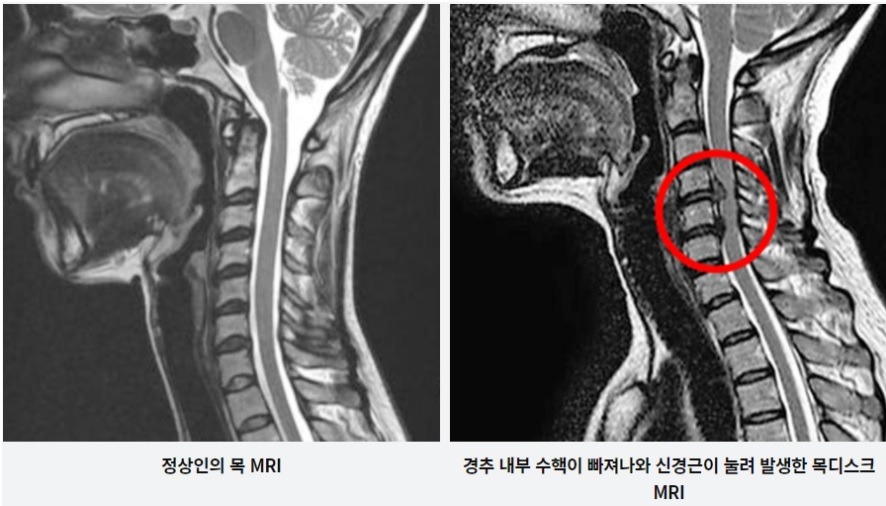

목 디스크는 목의 디스크(경추 디스크)에서 출현하는 질환으로, 경추 디스크 사이의 연골판이 터져 디스크 내부 물질이 경추 신경을 자극해 통증이나 저림증 등의 증상을 유발 해요. 목 디스크는 일상생활에서의 안 좋은 자세나 많은 운동, 부상 등이 이유가 되는 것이 될 수 있기도하고, 시간이 지날수록 발생 확률이 높아져요. 목 디스크의 증상으로는 목 부위의 통증, 팔의 저림, 근육 약화 등이 있으며, 증상이 난폭한 경우 수술 등의 치료가 필요할 수 있어요. 그리하나 대개의 경우 치료 없이도 시간이 지나면 증상이 호전되는 경우가 대부분입니다.

추간판의 수핵이 빠지거나 퇴행성 경추증 및 경추관협착증 등으로 척수가 압박되면 대다수 팔에 힘이 빠지는 것을 느끼게 돼요. 척수가 눌리는 정도이기 때문에 한쪽 팔만 마비될 수 있고요. 하지마는 양팔의 감각이 둔해지고 눈을 감고도 어지럽기 때문에 이러한 목 디스크 증상이 나타나면 무척 위험한 상태가 되기 때문에 빨리 치료가 필요해요.